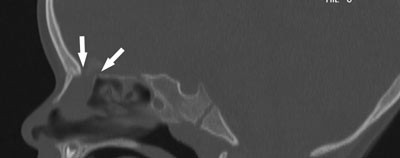

En to år gammel jente hadde renning fra venstre nesebor i ett år. Analyse på betasporprotein (β-trace) med en verdi på 14,6 mg/l var forenlig med rhinolikvoré (6). Hun hadde normalt utseende og normal psykomotorisk utvikling. Computertomografi viste en bløtdelsoppfylling i de fremre etmoidalcellene på venstre side, og diagnosen transetmoidal meningoencefalocele med likvoré ble stilt (fig 1).